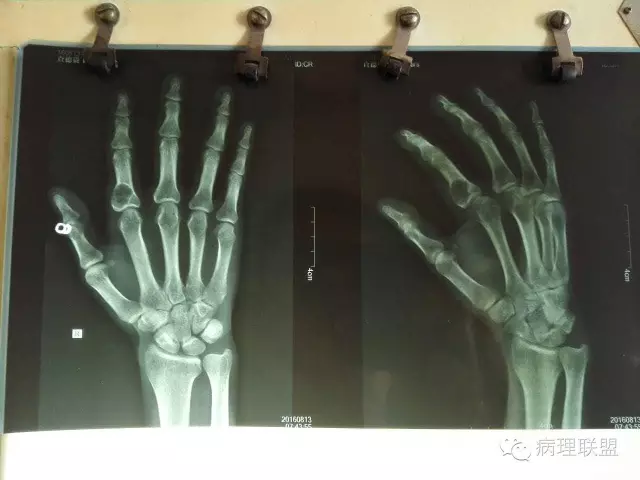

M/53 右食指包块(内生性软骨瘤)

食指为内生性软骨瘤,发生于指的内生软骨性肿瘤,即使有明显异性性,都不能随便打恶性。原则上。如果影像学有骨皮质破坏,侵袭性生长,那才考虑有没有恶性。

补充影像学。

影像学比较示溶骨性病变,骨皮质未破坏!